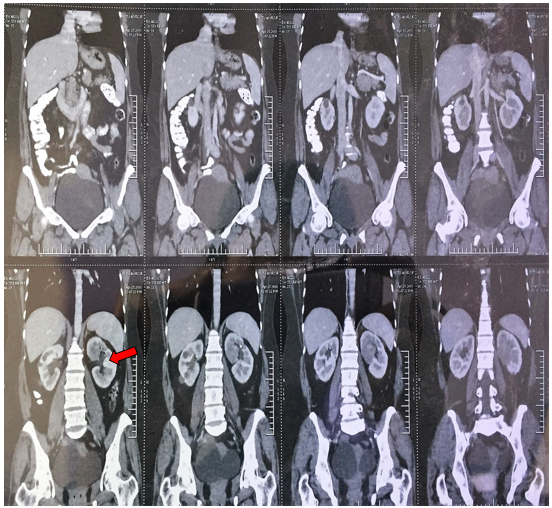

arising from the mid pole of the left kidney with small exophytic component in left perinephric space. Figure 2 No significant lymph nodes were noted.

Figure 2: CECT (W/A) shows a heterogeneous enhancing mass lesion measuring 44 (SI) x 42 (AP) x 35 (TR) mm arising from mid pole of left kidney with small exophytic component in left perinephric space.